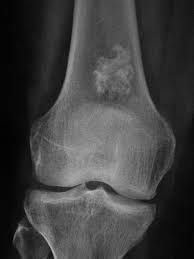

The exact cause of enchondroma is not known. However, it is thought to happen due to either of the following: Overgrowth of the cartilage that lines the ends of the bones Ongoing growth of original, embryonic cartilage